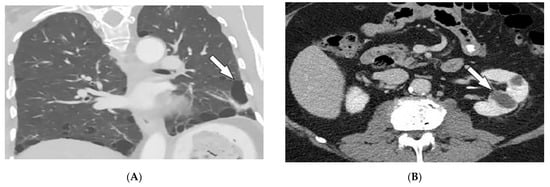

| Behcet’s disease | Oral and genital ulcers Ocular findings Vasculitis CNS lesions | Thickening of the aorta and SVC Bilateral pulmonary artery aneurysms Basal ganglia and brainstem lesions |

| Kaposi sarcoma | Erythematous or violaceous macules, plaques, nodules Pulmonary involvement Gastrointestinal involvement | Nodular enhancing masses Peribroncovascular nodules and halo sign |